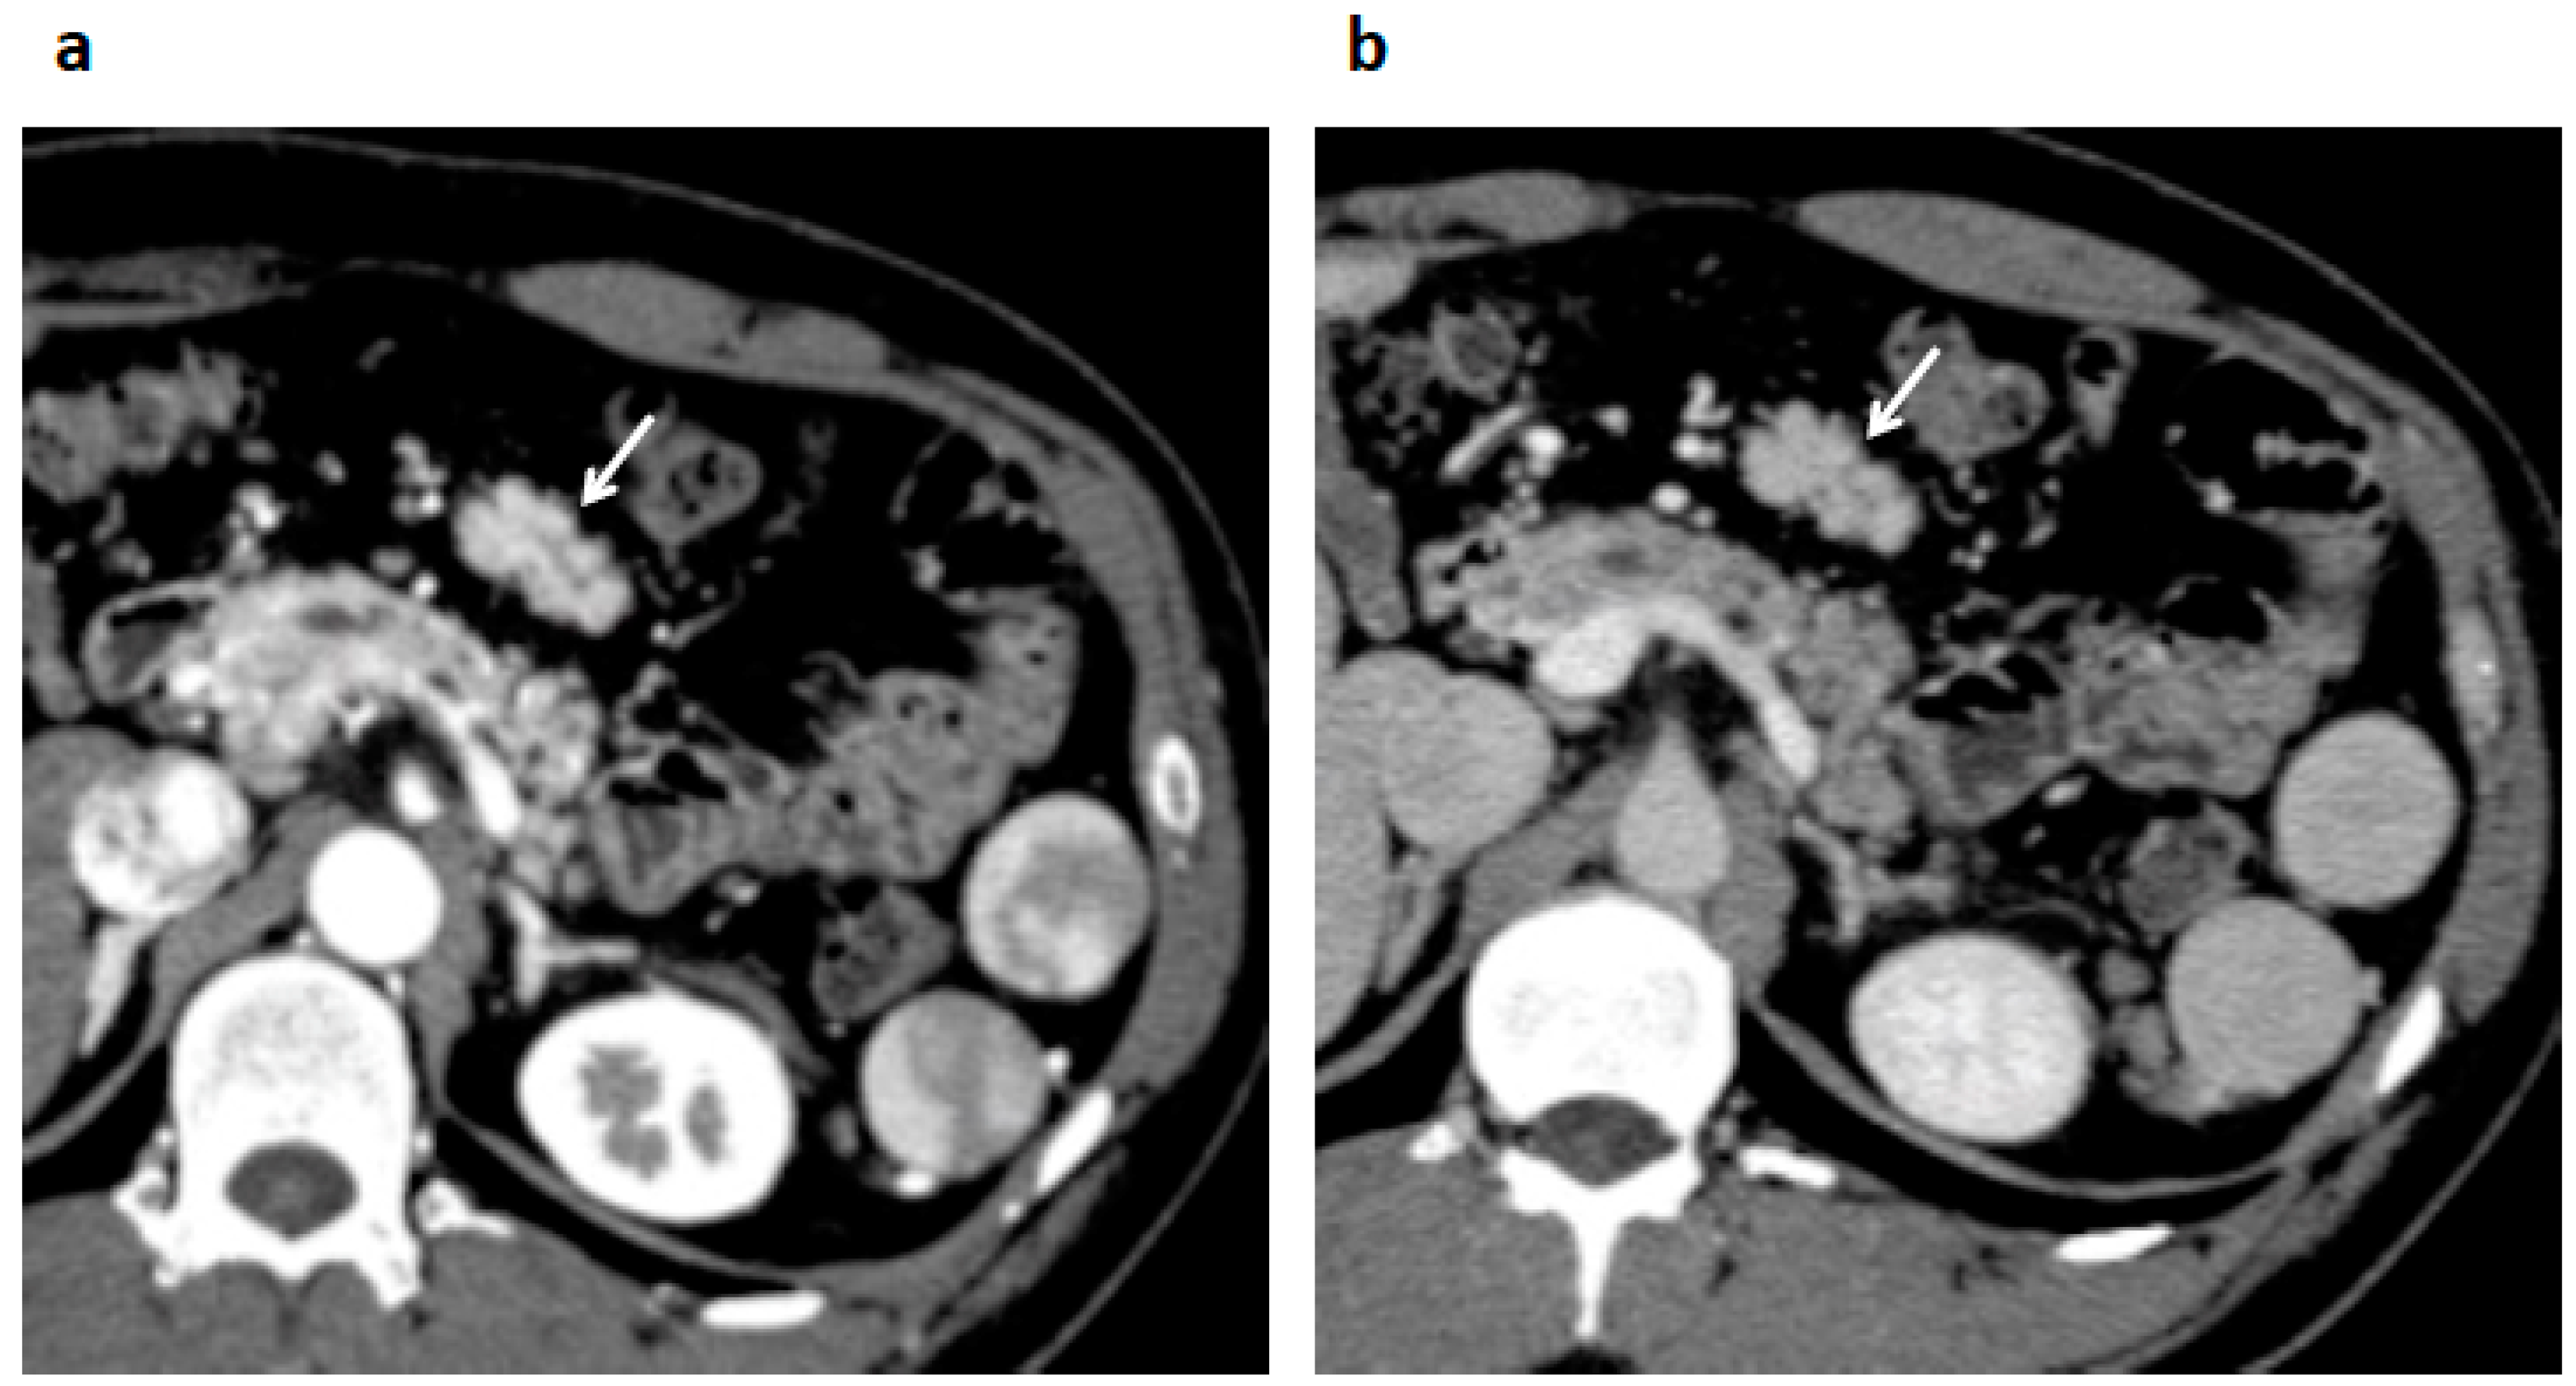

2. Case Presentation